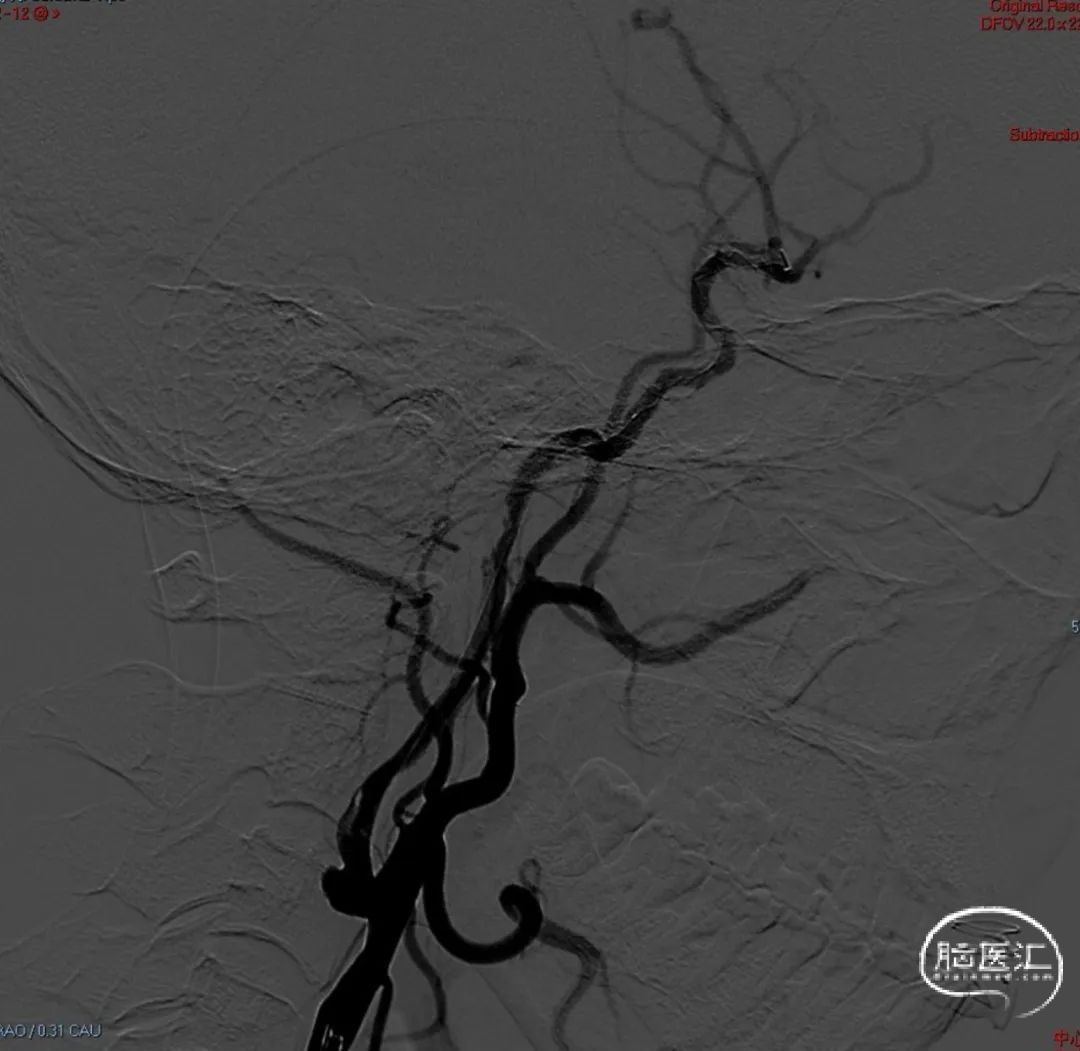

术后即刻影像。

支架植入后造影提示残余狭窄约10%。术中患者生命体征稳定,术后患者恢复良好出院,继续抗血小板聚集及他汀类药物治疗。